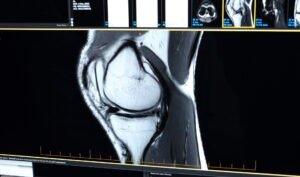

Patient-Specific Total Knee Replacement involves the use of pre-operative 3D planning and custom-designed surgical instruments, called patient-specific instrumentation (PSI). These guides are created from a CT scan of your full leg, extending from hip to ankle, to develop a highly detailed digital model of your knee.

Using the scan data, a highly accurate 3D digital model of your knee is created. This model becomes the foundation for your personalised surgical plan.